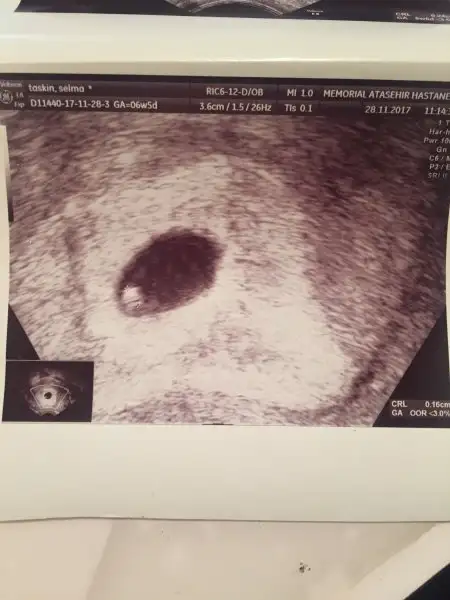

Merhaba anneler. Bu mesajı cok zor bir psikolojide yazıyorum. En son Perşembe günü kanama alanı azaldı ve bebeğim 2cm olmuş diye yazmıştım ve mutluluğumu paylaşmıştım. Ne yazikki aynı gece inanilmaz bir ağrı ile uyandım ve anlatamayacağım kadar çok kanamam oldu, hemen acile gittik ve yatış yapıldı. Sabaha kadar kanadım bir çok parçada düştü. Sabah ultrason kontrolünde gündüz çok sağlıklı,kalp atışı çok iyi ve görüntüsü muhteşem olan bebeğim kesesi ile birlikte yok olmuştu. Düşük yapmışım. Kürtaj olmadım bir hafta sonra kontrole gidicem.4 gündür dünyadamıyım, yaşıyor muyum bilemiyorum. 5. Tüp bebek denememde ilk defa hamile kalmıştım. 20 gün az az kanamam vardı. Bir çok igne ve hap almama rağmen 8+3 Bebeğimi kayıp ettim. Şimdi tekrar sil baştan denemek ve acaba bir daha hamilelik şansını yakalayabilecek miyim diye düşünmek çok üzücü. Herşey Allahtan tabi. Ancak inanılmaz yıkım oldu. Psikolojimi nasıl düzelteceğimi bilemiyorum. Icimden hiç birşey yapmak gelmiyor. Sizleri de sıktım belki ama paylaşmak istedim. Dilerim hepiniz sağlıkla kucağınıza alırsınız bebeklerinizi. Sağlıkla güzel günler diliyorum hepinize. Hoşçakalın.